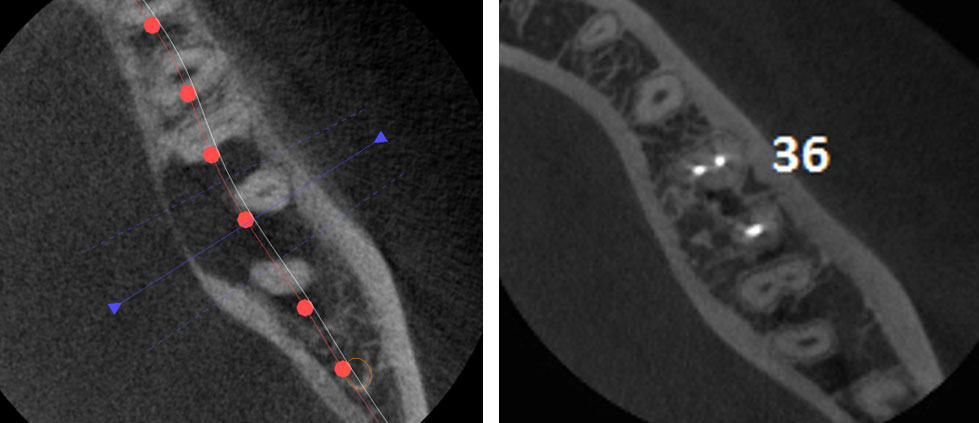

Age of patient: 15 years

Tooth: left mandibular first molar. Poor restorative prognosis. Very large lesion.

Work done: Obturation done after multiple calcium hydroxide dressings over 5 months and seeing lesion decrease in size. Fiber-post placed in distal canal. Core build-up done with Luxacore composite. Adv crown.

Notes: This is endo done for a “holding period” for implants later on. Healing of bone ensures a more favorable environment for implant placement.

Pre-op CBCT

3 year recall CBCT

Pre-op & 3 year recall